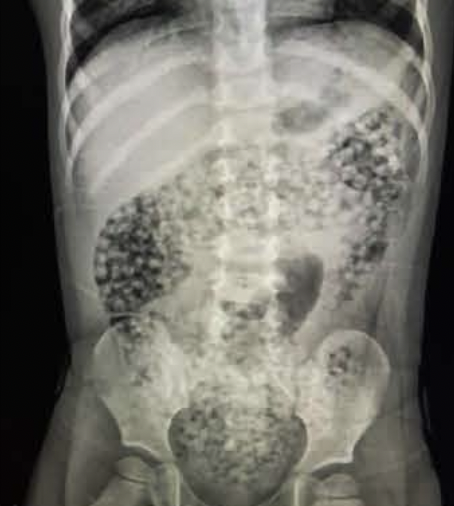

磁力球又稱磁力珠或巴克球,有多個顏色,且磁力相當強!因為有磁力可以經過揉捏變化成各種形狀的關係,很多人會買來讓孩子發揮創意製作成不同形狀,但其實磁力球是相當危險的!因為體積很小,容易被孩子誤食,當磁力球被吞到孩子腸道中容易吸在一起造成腸穿孔的危險,若遇到腸穿孔的狀況是需要進行開腹手術將其取出,是非常危險的玩具。

於2017至2021年間,因誤食磁力球而身亡的案件就有7件,超過2000名孩童因此送醫,家長千萬不可大意!